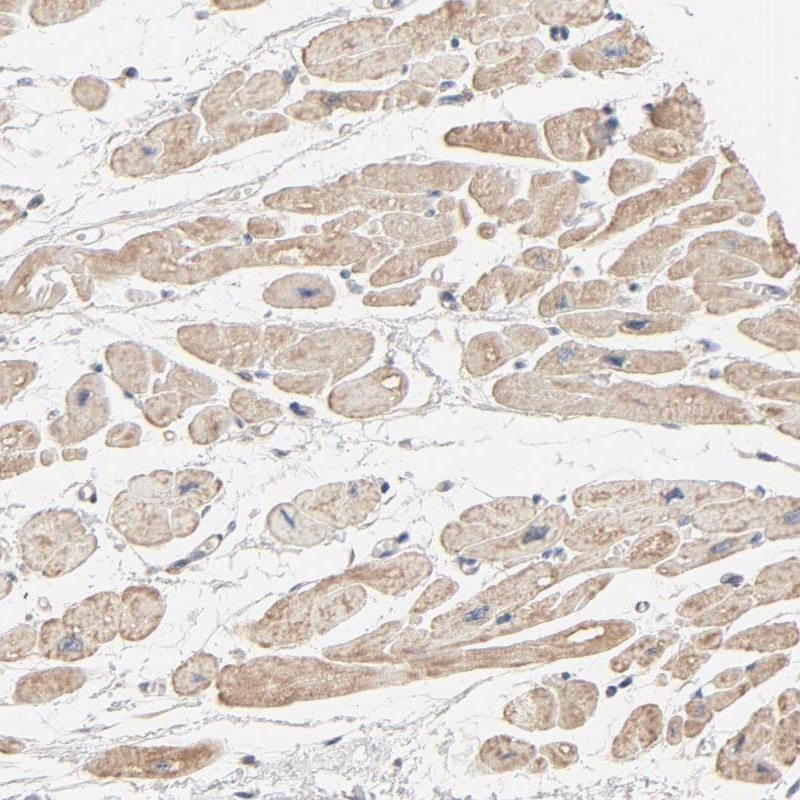

Immunohistochemical staining of human heart muscle shows moderate cytoplasmic positivity in myocytes.